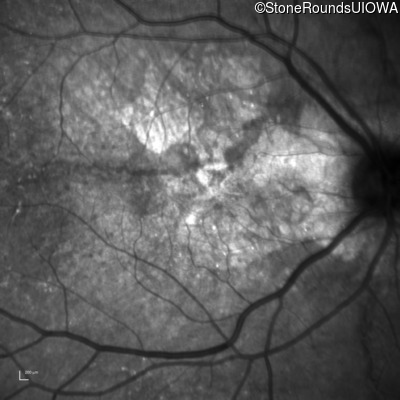

Infrared Fundus Photograph - Left - 20/25 +3

Exemplar